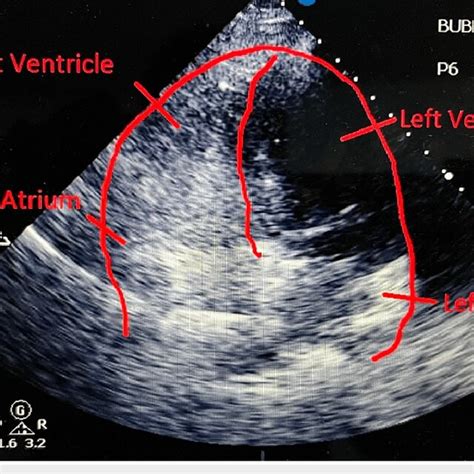

640×640

researchgate.net

Transthoracic echocardiogram with bubble study postprocedur…